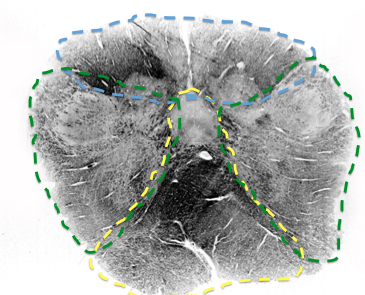

Blue?

top of Caudal medulla

Posterior spinal a.

Green?

Vertebral a.